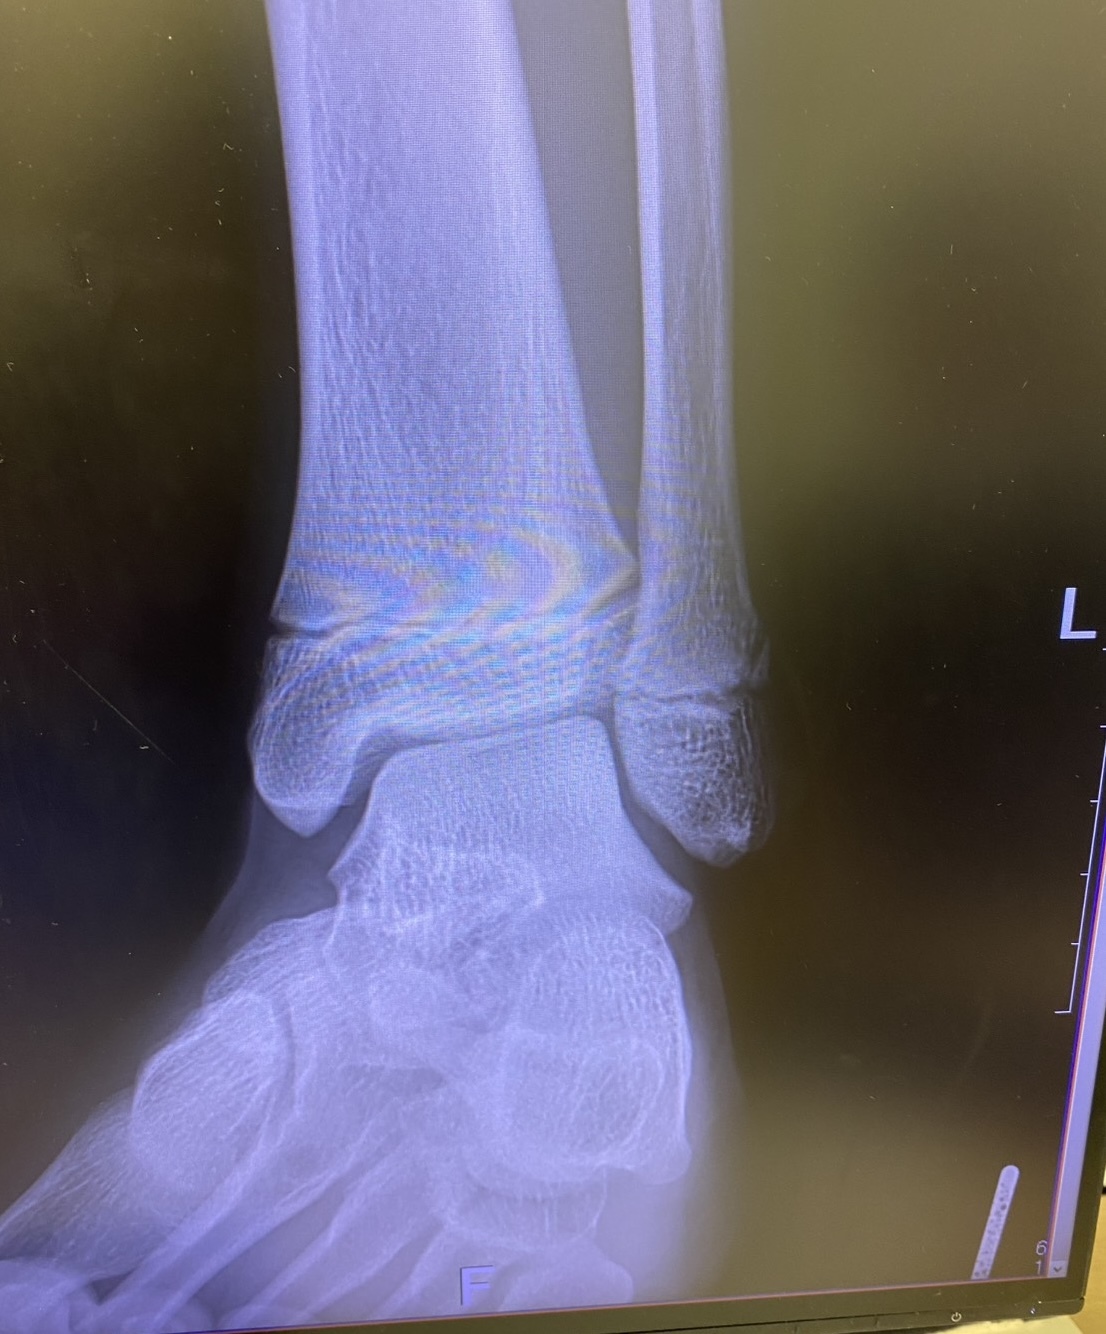

骨折を伴う骨端線損傷と判断し

近隣整形外科に対診。

結果、予想通り骨折と診断。